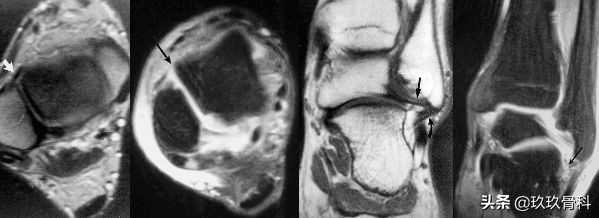

- 合并距骨关节面的骨软骨切线骨折

- MRI

- 关节软骨和骨软骨损伤

踝关节撞击综合征▲▲▲

1950 WOLIN首先描述踝关节内半月板样损伤。1991 ANDREWS确认上述损伤是因距腓前韧带撕裂后断端嵌入踝关节前外侧沟中形成,并报告切除这种损伤可缓解踝关节肿痛。

1991 FERKEL通过组织病理学分析证明其为增厚的滑膜组织。从此开始将踝关节无骨折脱位的长期肿痛称为踝关节软组织撞击综合征。

体征:前内或前外间隙压痛;部分病人关节肿痛、背伸受限、不能下蹲。

诊断:踝关节扭伤史、X线无明显异常、踝前疼痛肿胀、经休息及非手术治疗不明显者应考虑为本病。